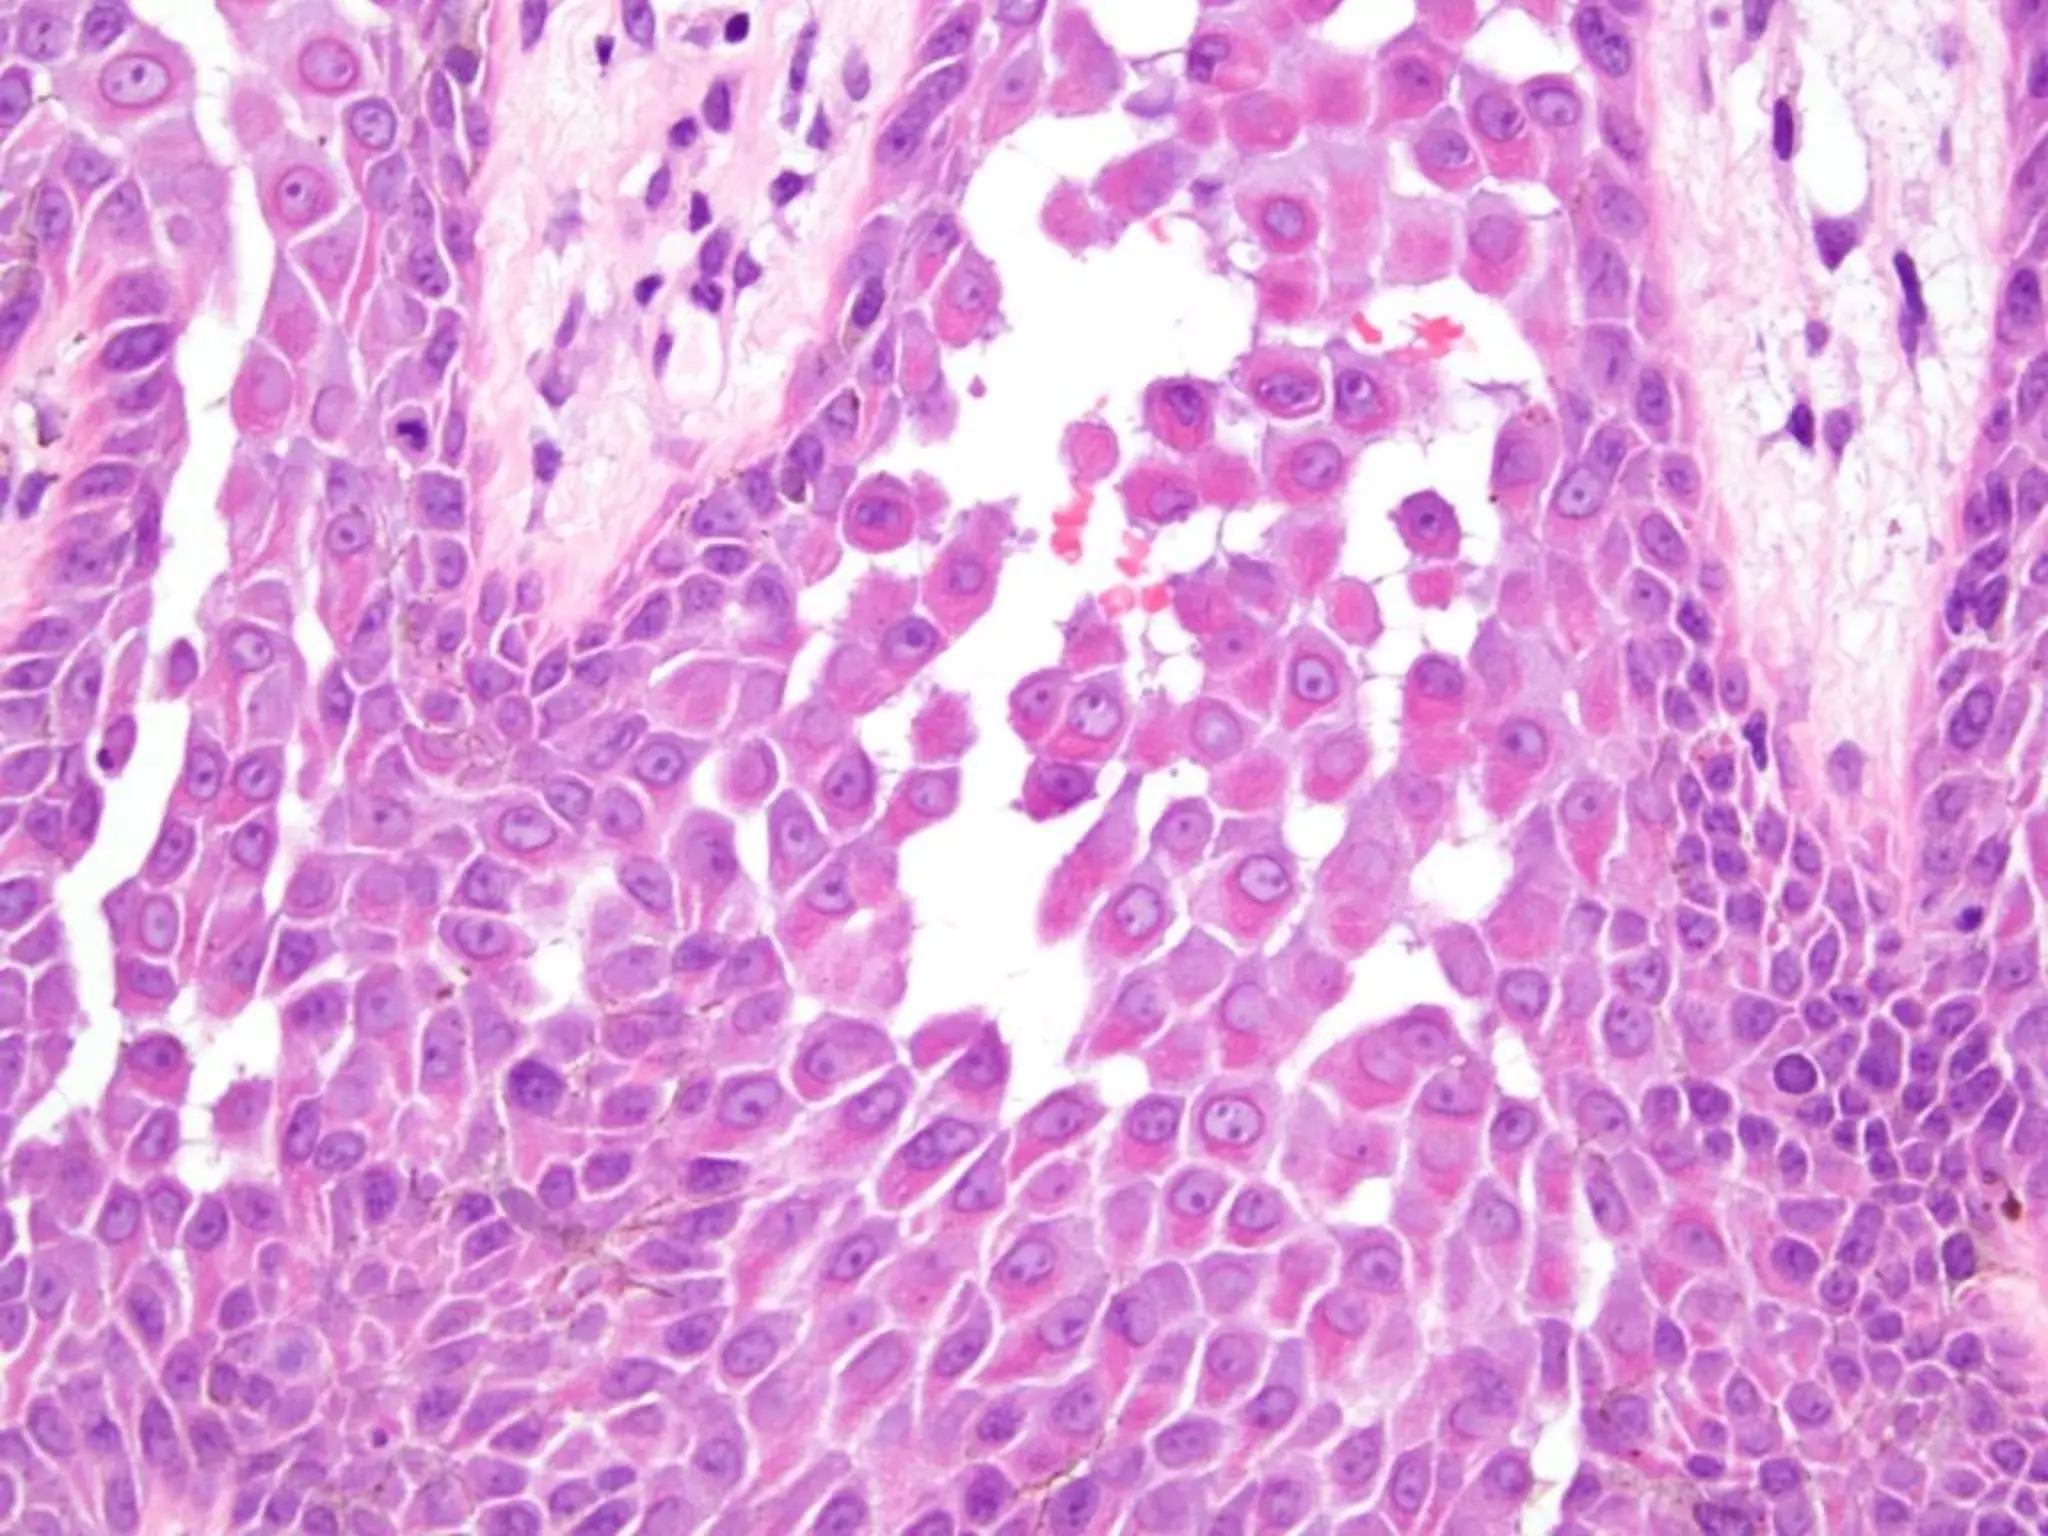

The document provides an overview of dermatopathology, including methods and techniques for skin biopsies such as shave, punch, and ellipse methods. It discusses key terms associated with dermatopathology, such as acantholysis and granulation tissue. Additionally, it references presentations by professionals in the field and essential dermatology resources.